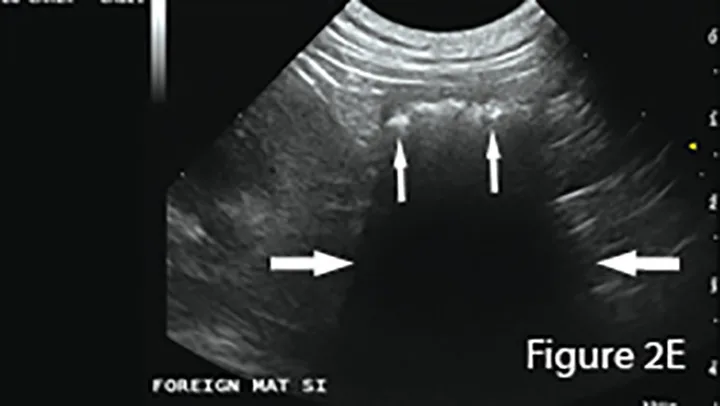

A longitudinal segment of severely fluid-distended small intestine (arrows) adjacent to normal bowel seen in transverse sections (*), suggesting obstruction. The greatly dilated lumen (L) shows speckled, echogenic fluid with readily observable movement in real-time examination. Potential cause (eg, foreign material, mass, intussusception) should be investigated. (K = caudal pole of kidney)

Ultrasound of small intestinal foreign material typically appears hyperechoic (small arrows) with strongly distal acoustic shadowing (large arrows), although this can vary depending on composition, shape, and number. Foreign material will not change shape with peristalsis and often has an organized surface for differentiation from intraluminal gas, which typically causes reverberation artifacts (ie, comet tails).